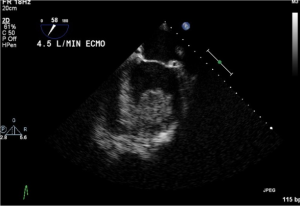

In special configuration when RVAD used as ECMO the oxygenated blood is delivered to the pulmonary artery so the blood bypass only the right heart (Figure 5).

Cardiovascular system management: systemic perfusion and intravascular volume should be maintained. Volume status can be assessed clinically by urine output, central venous pressure, physical signs of perfusion, and body weight. Good cardiac output should be achieved with inotropic agents. Echocardiography should be performed to assess the heart’s condition, and heart recovery, rule out thrombosis, and should be repeated if any significant changes in the ECMO flow, or deterioration in the patient’s hemodynamics.